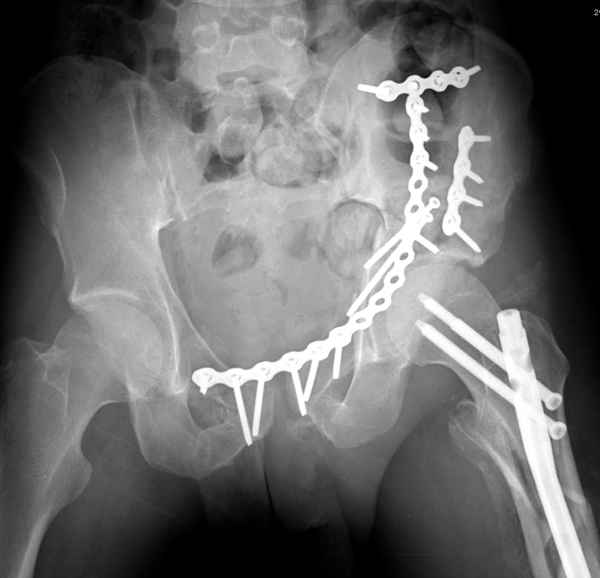

Здесь несколько вариантов двухколонных свежих переломов, которые были оперированы из одного-заднего, а также из двух: переднего и заднего доступов.

Имя     : 1 Both column one incision.jpg

Тип     : image/jpeg

Имя     : 2 Both column one incision.jpg